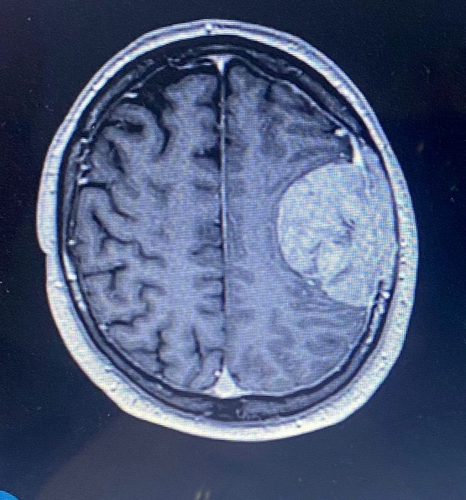

He was blue-lighted to Southmead Hospital, Bristol, where a CT scan revealed a mass on the brain.

Stuart's speech fluctuated, and he was diagnosed with a meningioma - a slow-growing tumor.

After being blue-lighted to Southmead Hospital, a CT scan revealed that Stuart had a mass on the brain.

Stuart’s speech fluctuated, and he was prescribed steroids. Surgeons advised that, because there was no evidence of cancer elsewhere, it was likely to be a slow-growing tumor that Stuart could have had for years.

It had not grown into his brain but was attached to the membrane and skull, part of which had to be removed and reconstructed using bone cement.